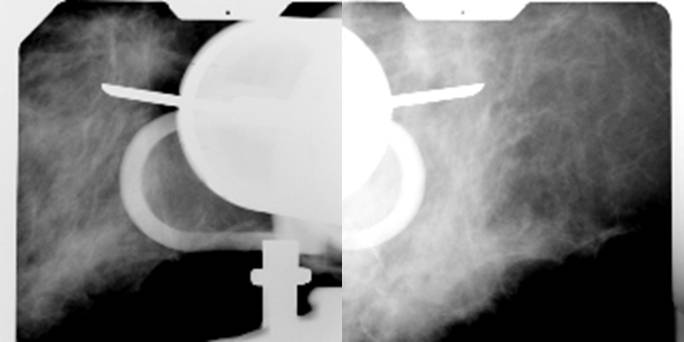

- Comprimir la zona a biopsiar i realitzar una exposició sense bascular el tub per assegurar-se que estem a la zona d’interès. La lesió ha d’estar al centre de la finestra estereotà xica.

- Realitzar dues projeccions de la zona a +15º i -15º.

- Plaques de comprovació de la situació de la cà nula +15º i -15º.